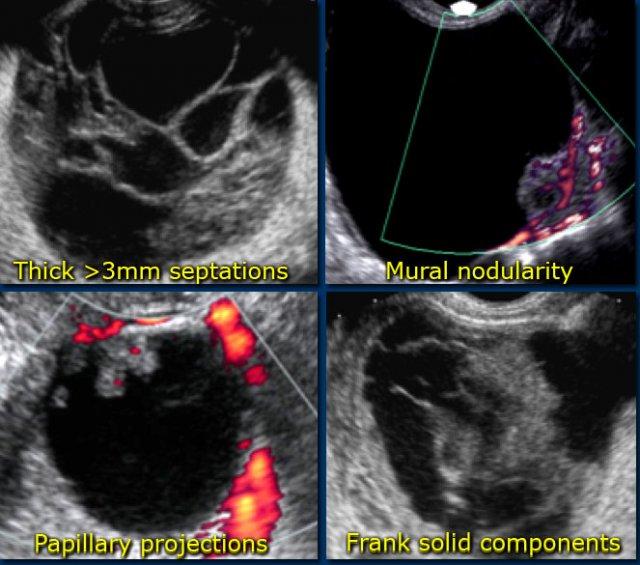

Các dấu hiệu gợi ý khả năng tân sinh:

Ngoài ra, khả năng tổn thương tân sinh là ác tính cũng tăng theo kích thước tổn thương. - Vách ngăn có mạch máu

Sự hiện diện của vách ngăn gợi ý khả năng tân sinh. Khi vách ngăn có độ dày hơn 3mm và có mạch máu rõ – mặc dù không đặc hiệu – cả hai đặc điểm này đều làm tăng khả năng tổn thương tân sinh là ác tính. - Thành phần đặc có mạch máu

Các nốt có mạch máu, nhú nhô vào lòng nang, hoặc khối đặc thực sự đều làm tăng khả năng bản chất tân sinh. - Thành dày, không đều có mạch máu

Các tổn thương có thành mỏng thường lành tính hơn và các tổn thương có thành dNguy cơ thấp hay Nguy cơ cao